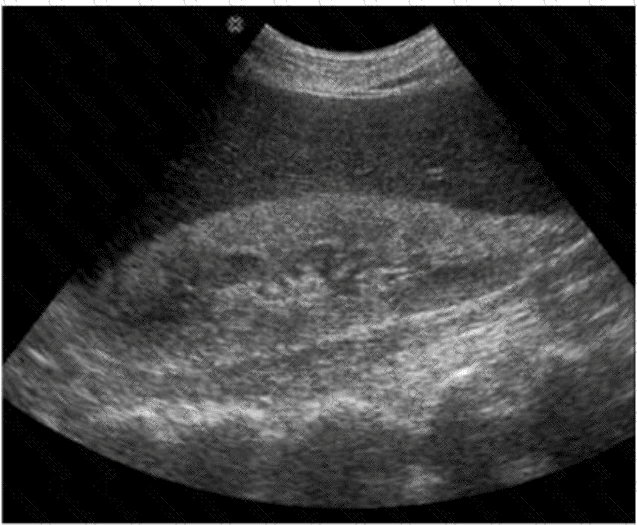

The ultrasound image demonstrates diffuse increased echogenicity of the liver parenchyma with posterior beam attenuation (acoustic shadowing), findings that are consistent with hepatic steatosis (fatty liver disease). The liver appears brighter than normal, and the vascular markings, particularly of the portal veins, are obscured due to the increased parenchymal echogenicity.

Classic sonographic features of hepatic steatosis include:

Diffuse hyperechogenicity (“bright liver”)

Poor visualization of intrahepatic vessels and diaphragm

Posterior acoustic attenuation

Increased hepatic echogenicity relative to the renal cortex